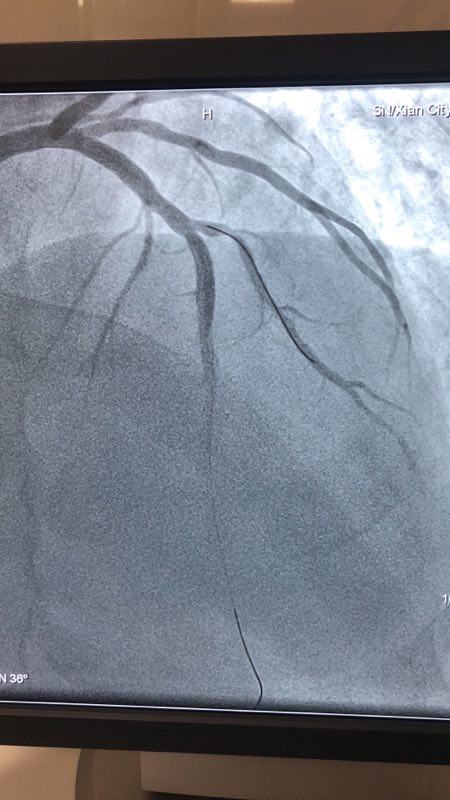

此例患者,男性,56岁,11年前因心绞痛在西京医院行冠状动脉造影检查后于D1对角支置入1枚支架治疗。术后患者口服“阿司匹林肠溶片、氯吡格雷、阿托伐他汀”等药物治疗1年后自行停药,并有长期大量吸烟史。2018年12月24日患者突发胸痛、胸闷,急来21点游戏攻略站 就诊。急诊行冠状动脉造影检查提示D1对角支原支架内再狭窄70%-90%。急救中心主任张誉洋副主任医师考虑到第一对角支管径较小,于原支架内再次置入支架引起再狭窄的风险极大,遂建议应用药物涂层球囊扩张术治疗D1对角支原支架内狭窄。与患者充分沟通后,于12月27日行冠脉药物涂层球囊PTCA术治疗,造影显示血管开通情况良好,术后患者症状明显改善。